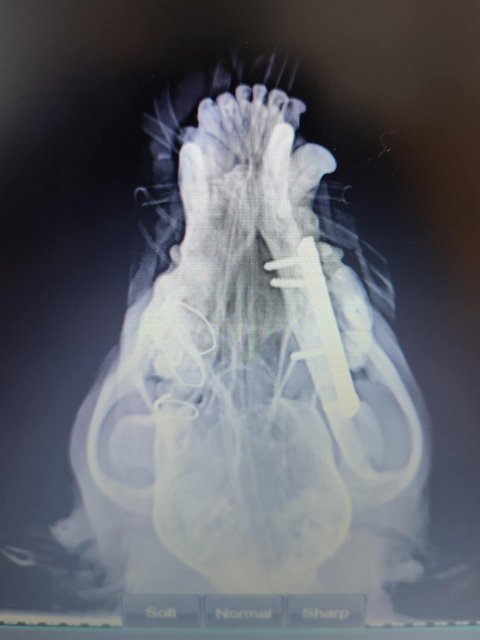

Röntgenbilder zeigten das Ausmaß der Zerstörung des Unterkiefers und den Bruch eines Beines.

Dieser Hund muss grausame Schmerzen haben, Zähne sind aus der Verankerung gerissen und sein Gesichtsschädel ist nicht mehr symmetrisch. Ein großes Stück des Unterkiefers ist komplett abgebrochen.

Es braucht sicher viel Geschick, um das wieder so zusammenzusetzen, dass der Hund später problemlos fressen kann.

Camush Kopf ist wieder symmetrisch, der Kiefer wird jetzt mit Platte und Verdrahtung zusammengehalten und ein paar Zähne fehlen jetzt.